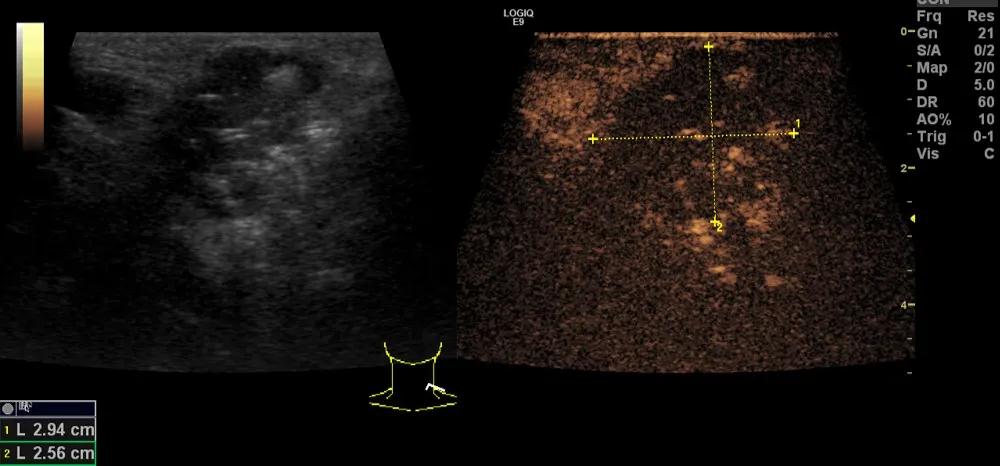

第三例是甲状腺癌患者,双侧甲状腺癌切除术后、碘治疗后一年余效果欠佳,超声显示左颈3区3枚低回声结节,穿刺示甲状腺乳头状癌转移。患者不愿意手术,希望采取局部治疗。对病灶进行液体隔离后采取热消融术,由于淋巴结较小,热消融一分钟左右完全灭活,术后增强影像显示没有脏器充填。

(病例3图例)